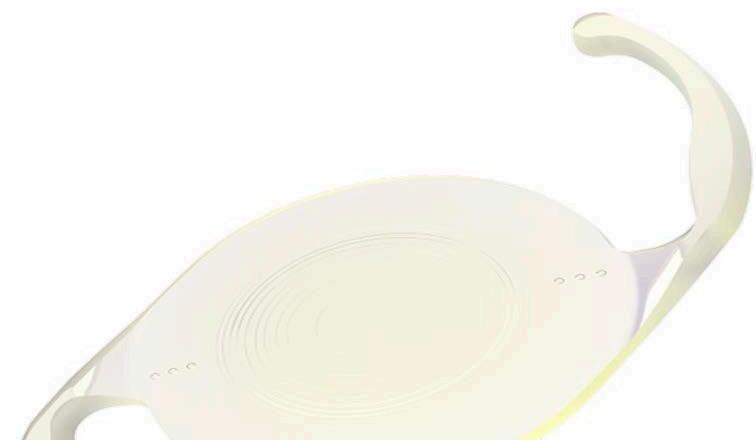

Clareon® PanOptix® de Alcon: Esta innovadora lente trifocal representa la evolución del reconocido modelo PanOptix® , ahora combinada con el nuevo material Clareon®. El Clareon® es un acrílico hidrofóbico de última generación, con una pureza y claridad superior, que elimina virtualmente la aparición de “glistenings” o microvacuolas. Esto se traduce en una mayor estabilidad refractiva y una calidad visual sostenida a largo plazo. La óptica trifocal permite a los pacientes obtener una visión excelente a distancia, intermedia (ideal para computadoras) y cercana (lectura), con una mínima dependencia de anteojos. En el marco del congreso, se presentaron estudios multicéntricos que mostraron altos niveles de satisfacción y nitidez visual incluso en condiciones de baja iluminación, posicionando a esta lente como una de las más completas para pacientes activos con altas expectativas visuales.

Resumen de Novedades - Congreso ASCRS 2025: Innovación y Tecnología en Cirugía del Segmento Anterior.

RayOne Galaxy de Rayner : Una de las grandes novedades del ASCRS 2025, fue presentada como la primera lente intraocular diseñada con el apoyo de inteligencia artificial. Se trata de una lente no difractiva con óptica espiral progresiva, lo que permite una transición suave y continua entre diferentes distancias focales sin los efectos secundarios típicos de otras lentes multifocales, como halos o deslumbramientos nocturnos.

Su diseño aprovecha algoritmos de inteligencia artificial entrenados en miles de casos reales para optimizar la distribución de luz en función del tamaño pupilar y las condiciones de iluminación. Además, la lente se inyecta mediante el sistema RayOne preloaded , que asegura una implantación precisa y segura, reduciendo el tiempo quirúrgico.

Esta LIO se perfila como una opción atractiva para pacientes que buscan independencia de gafas con excelente calidad visual en todas las distancias, incluso en pacientes con córneas ligeramente irregulares.

Apthera IC-8 de Bausch + Lomb : Esta lente de apertura pequeña no tórica está diseñada para pacientes con astigmatismo corneal de hasta 1.5 D, ofreciendo una solución eficaz para la presbicia y mejorando la calidad visual en condiciones de baja iluminación.